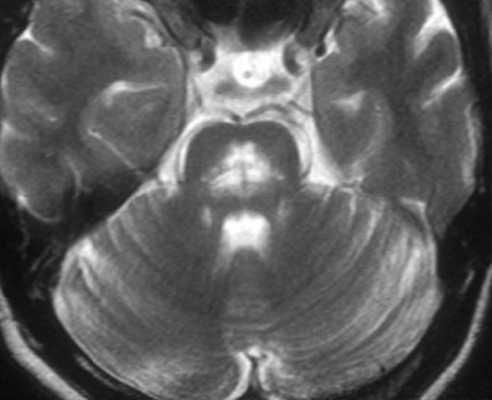

Гипертрофическая дегенерация ядер оливы считается специфической формой транссинаптической гипертрофической дегенерации и развивается вследствие неспецифического повреждения денто-рубро-оливарного пути. Хотя это состояние у детей считается редким, сообщается о его превалировании у пациентов с метаболическими заболеваниями, а также после операции по поводу опухолей задней черепной ямки. На МРТ выявляются Т2-гиперинтенсивные очаги, часто с билатеральным и симметричным увеличением оливарных ядер. Они начинают появляться в течение месяца после острого события и в течение 3-4 лет имеют тенденцию к разрешению.

К посттравматическим изменениям можно отнести гипертрофическую дегенерацию оливкового ядра, которая наблюдается крайне редко чрез 3-6 месяцев после травмы. При МРТ головного мозга выявляется повышенный сигнал на Т2-взвешенных МРТ с одной или двух сторон.

МРТ головного мозга. Т2-взвешенная аксиальная МРТ. Гипертрофическая дегенерация левого оливкового ядра.